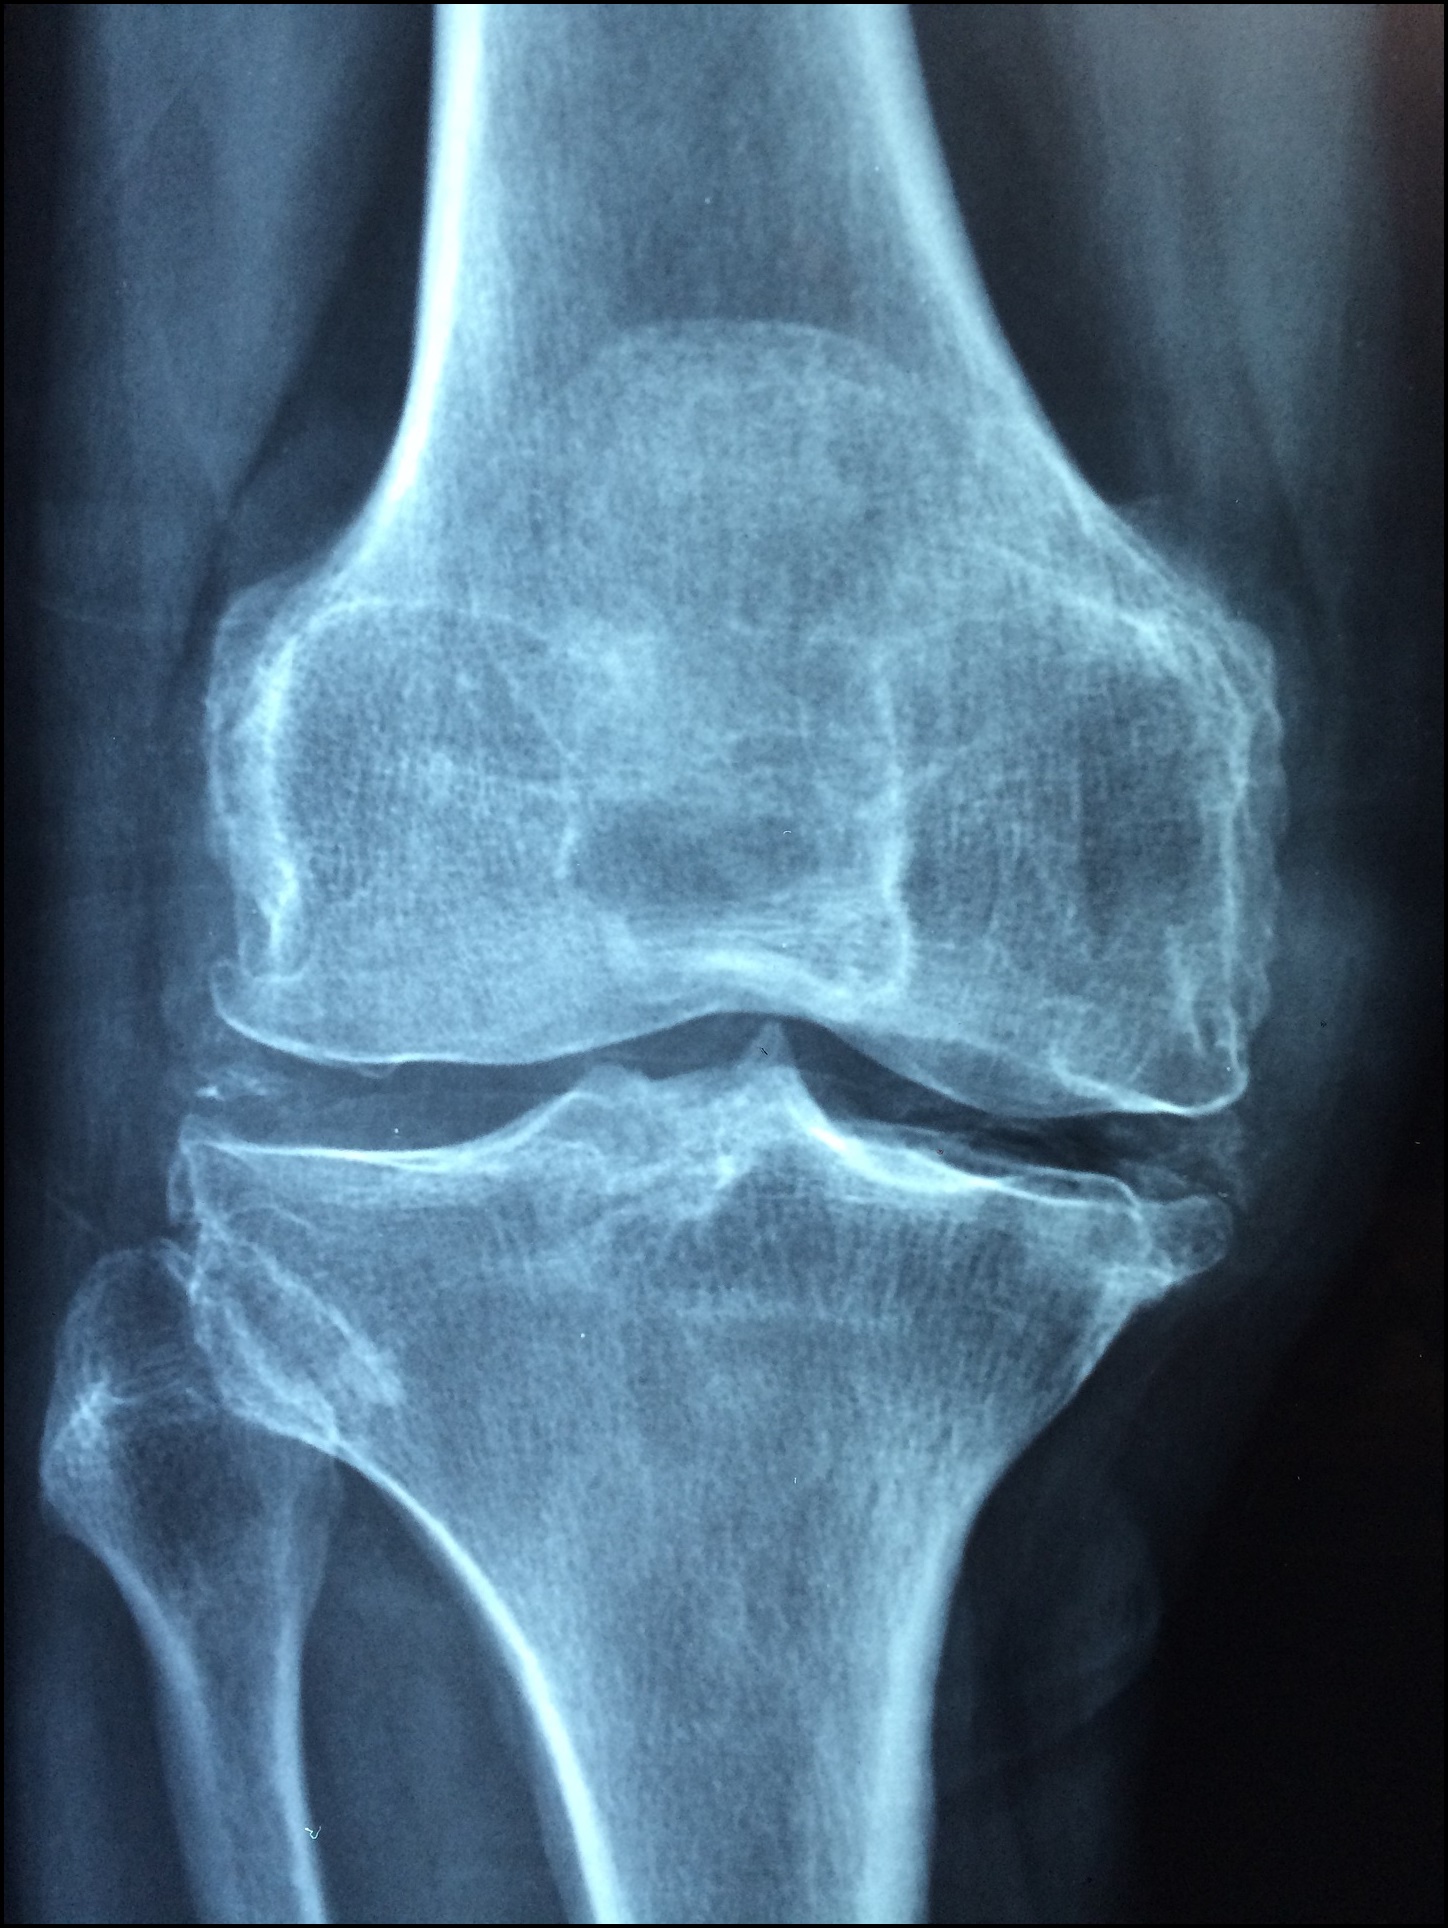

칼슘은 UP 시켜주고 나트륨은 DOWN 시켜서 뼈 건강에 도움을 주는 바다의 생선 박대입니다.

박대는 칼슘이 풍부하기 때문에 우리 몸의 골밀도 유지와 골다공증 예방 등 뼈건강 유지에 도움을 줄 수 있습니다.

또한 나트륨을 과다 섭취하면 뼈가 약해지고 골절 위험이 높아지는데 박대에 있는 풍부한 칼륨 성분은 체내 나트륨을 배출시켜 주는 역할을 한다고 합니다.

때문에 박대 섭취 시 칼슘은 높여주고 나트륨은 줄여서 뼈 건강을 지키는데 도움을 받을 수 있는 것입니다.

나트륨 과잉 섭취는 체내 염증을 유발하고 뼈 건강을 악화시키는 요인중 하나입니다.

칼륨이 풍부한 박대를 자주 섭취하면 이러한 뼈 건강에 많은 도움이 될 수 있습니다.